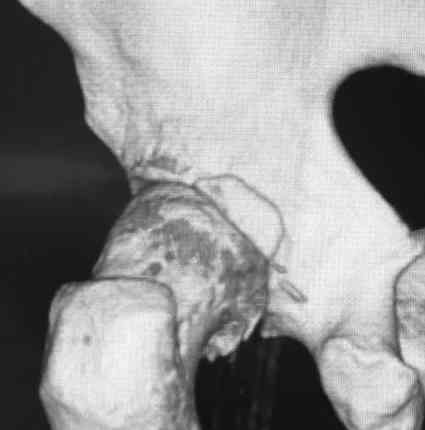

[Ortho] Pipkin II

Стоило ли заниматься остеосинтезом в этом случае?

Мужчина, 50 лет, активный, падение с высоты. При поступлении вправление

вывиха, других повреждений нет Без значимой сопутствующей патологии, не

курит. Стоило ли выполнять остеосинтез при таком оскольчатом переломе

или сразу пойти на ТНА?